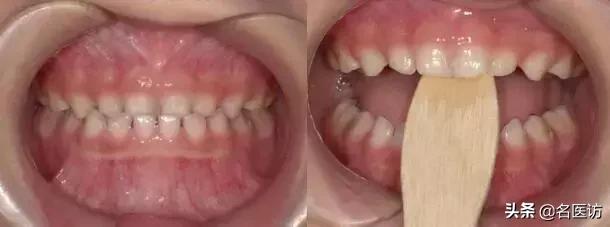

牙齿矫正前后

牙齿矫正前后对比图

咬撬法

没得错,就是喊你咬棍棍儿!选择压舌板或牙刷柄,每天咬撬木板三次,每次大约2分钟(约20下),每两周复诊,1-3个月就阔以有效纠正“地包天”。